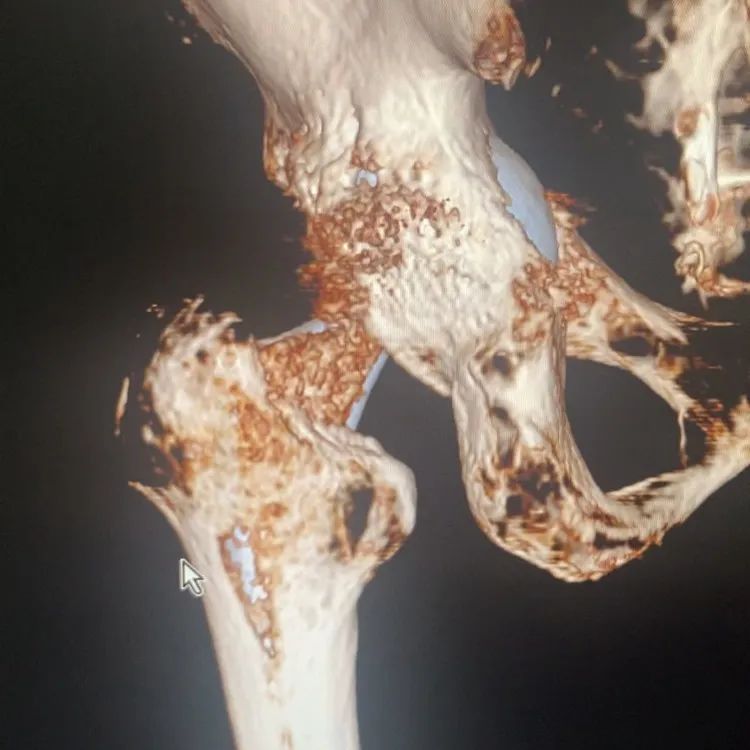

经过骨科团队详细检查后,认为“患者髋部疼痛及功能障碍是由于人工关节髋臼松动假体松动导致。人工髋臼移位明显,伴随髋臼周围大量骨溶解、骨吸收。重建稳固的髋臼是手术的首要任务,大量骨溶解、骨吸收给手术带来相当大的挑战。

术前,手术团队运用3D打印技术,精准打印患者骨缺损情况,并个体化设计手术方案,选择人工假体组件;体外模拟手术,以确保手术过程精准、顺利进行。

术前照片